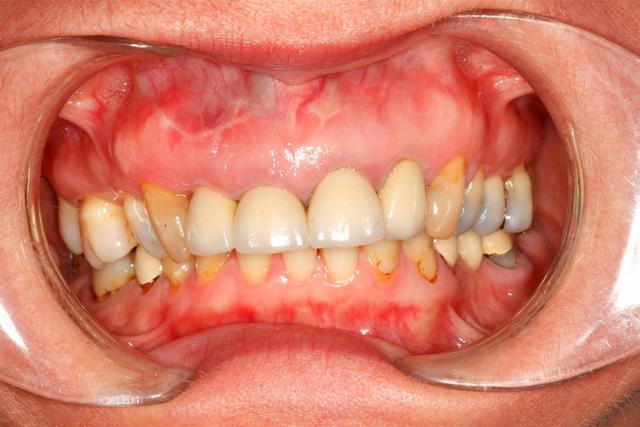

J'ai placé des provisoires de 13 à 23 suite à

l'élongation de 13 à 23 et apectomie 12.

C'est une patiente...

Avant: difficulté musculaire pour mastiquer, raideurs, limitation de mouvement, fatigue rapide.

Après, non, tout va bien.

Tu arrives à cela avec ton truc en haut. Ah oui, ma patiente fonctionne avec 24h/24h, c'est fixe mais 100% réversible.